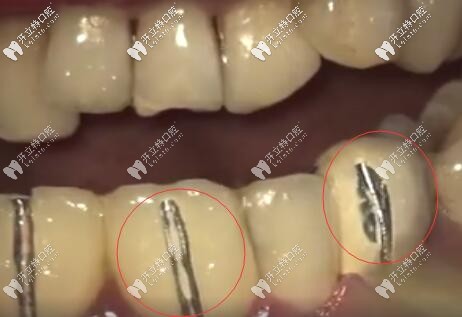

烤瓷牙牙齦黑線

因?yàn)槌霈F(xiàn)牙齦黑線也說(shuō)明烤瓷牙牙冠與牙根之間不密合,已經(jīng)有一條縫了,有了這條縫,食物殘?jiān)?、?xì)菌等都容易從這條縫進(jìn)入牙套里去。

從而讓里面的基牙發(fā)生齲壞,時(shí)間久了,這個(gè)牙就整個(gè)爛掉了,有些醫(yī)生技術(shù)不過(guò)比如備牙,粘結(jié),牙冠做的不合適,與牙根牙齦不密合,挺不過(guò)幾年都有可能出問(wèn)題。